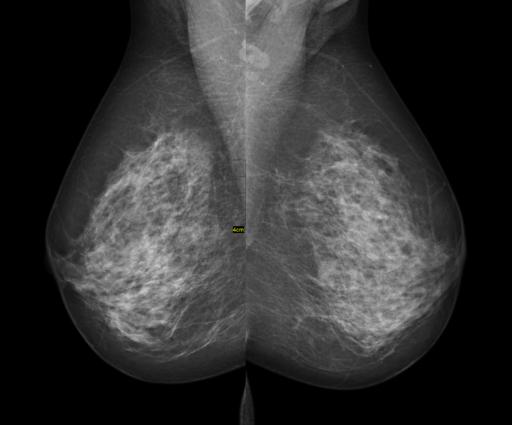

- Women with nondense breasts had fewer cancers identified initially (5.5% vs. 6.7%), and on interval examinations (1.2% vs. 2.8%) as compared to women with dense breasts, suggesting that breast density might be a marker for differences in a woman's physiologic responses.

- Tumors had smaller mean diameters and proportion of nodal involvement in non-dense breasts identified at the initial screening, but these differences were not found in tumors identified in interval examinations. This suggested that tumor growth, at least in the interval, was different for these two groups of women.

Mammography is less sensitive in identifying the disease in women with dense breasts, the more than doubling of the rate of interval detection rather than initial discovery attests to that. Whether the less favorable tumor characteristics at interval discovery are due to the time interval or to some differences in the biologic behavior of cancer based upon breast density is unknown. What does seem increasingly clear though is that women with dense breasts are a separate subpopulation, their tumors are harder to detect and seem to behave differently. We need to consider ways to improve their screening - a practical means of personalizing medicine.